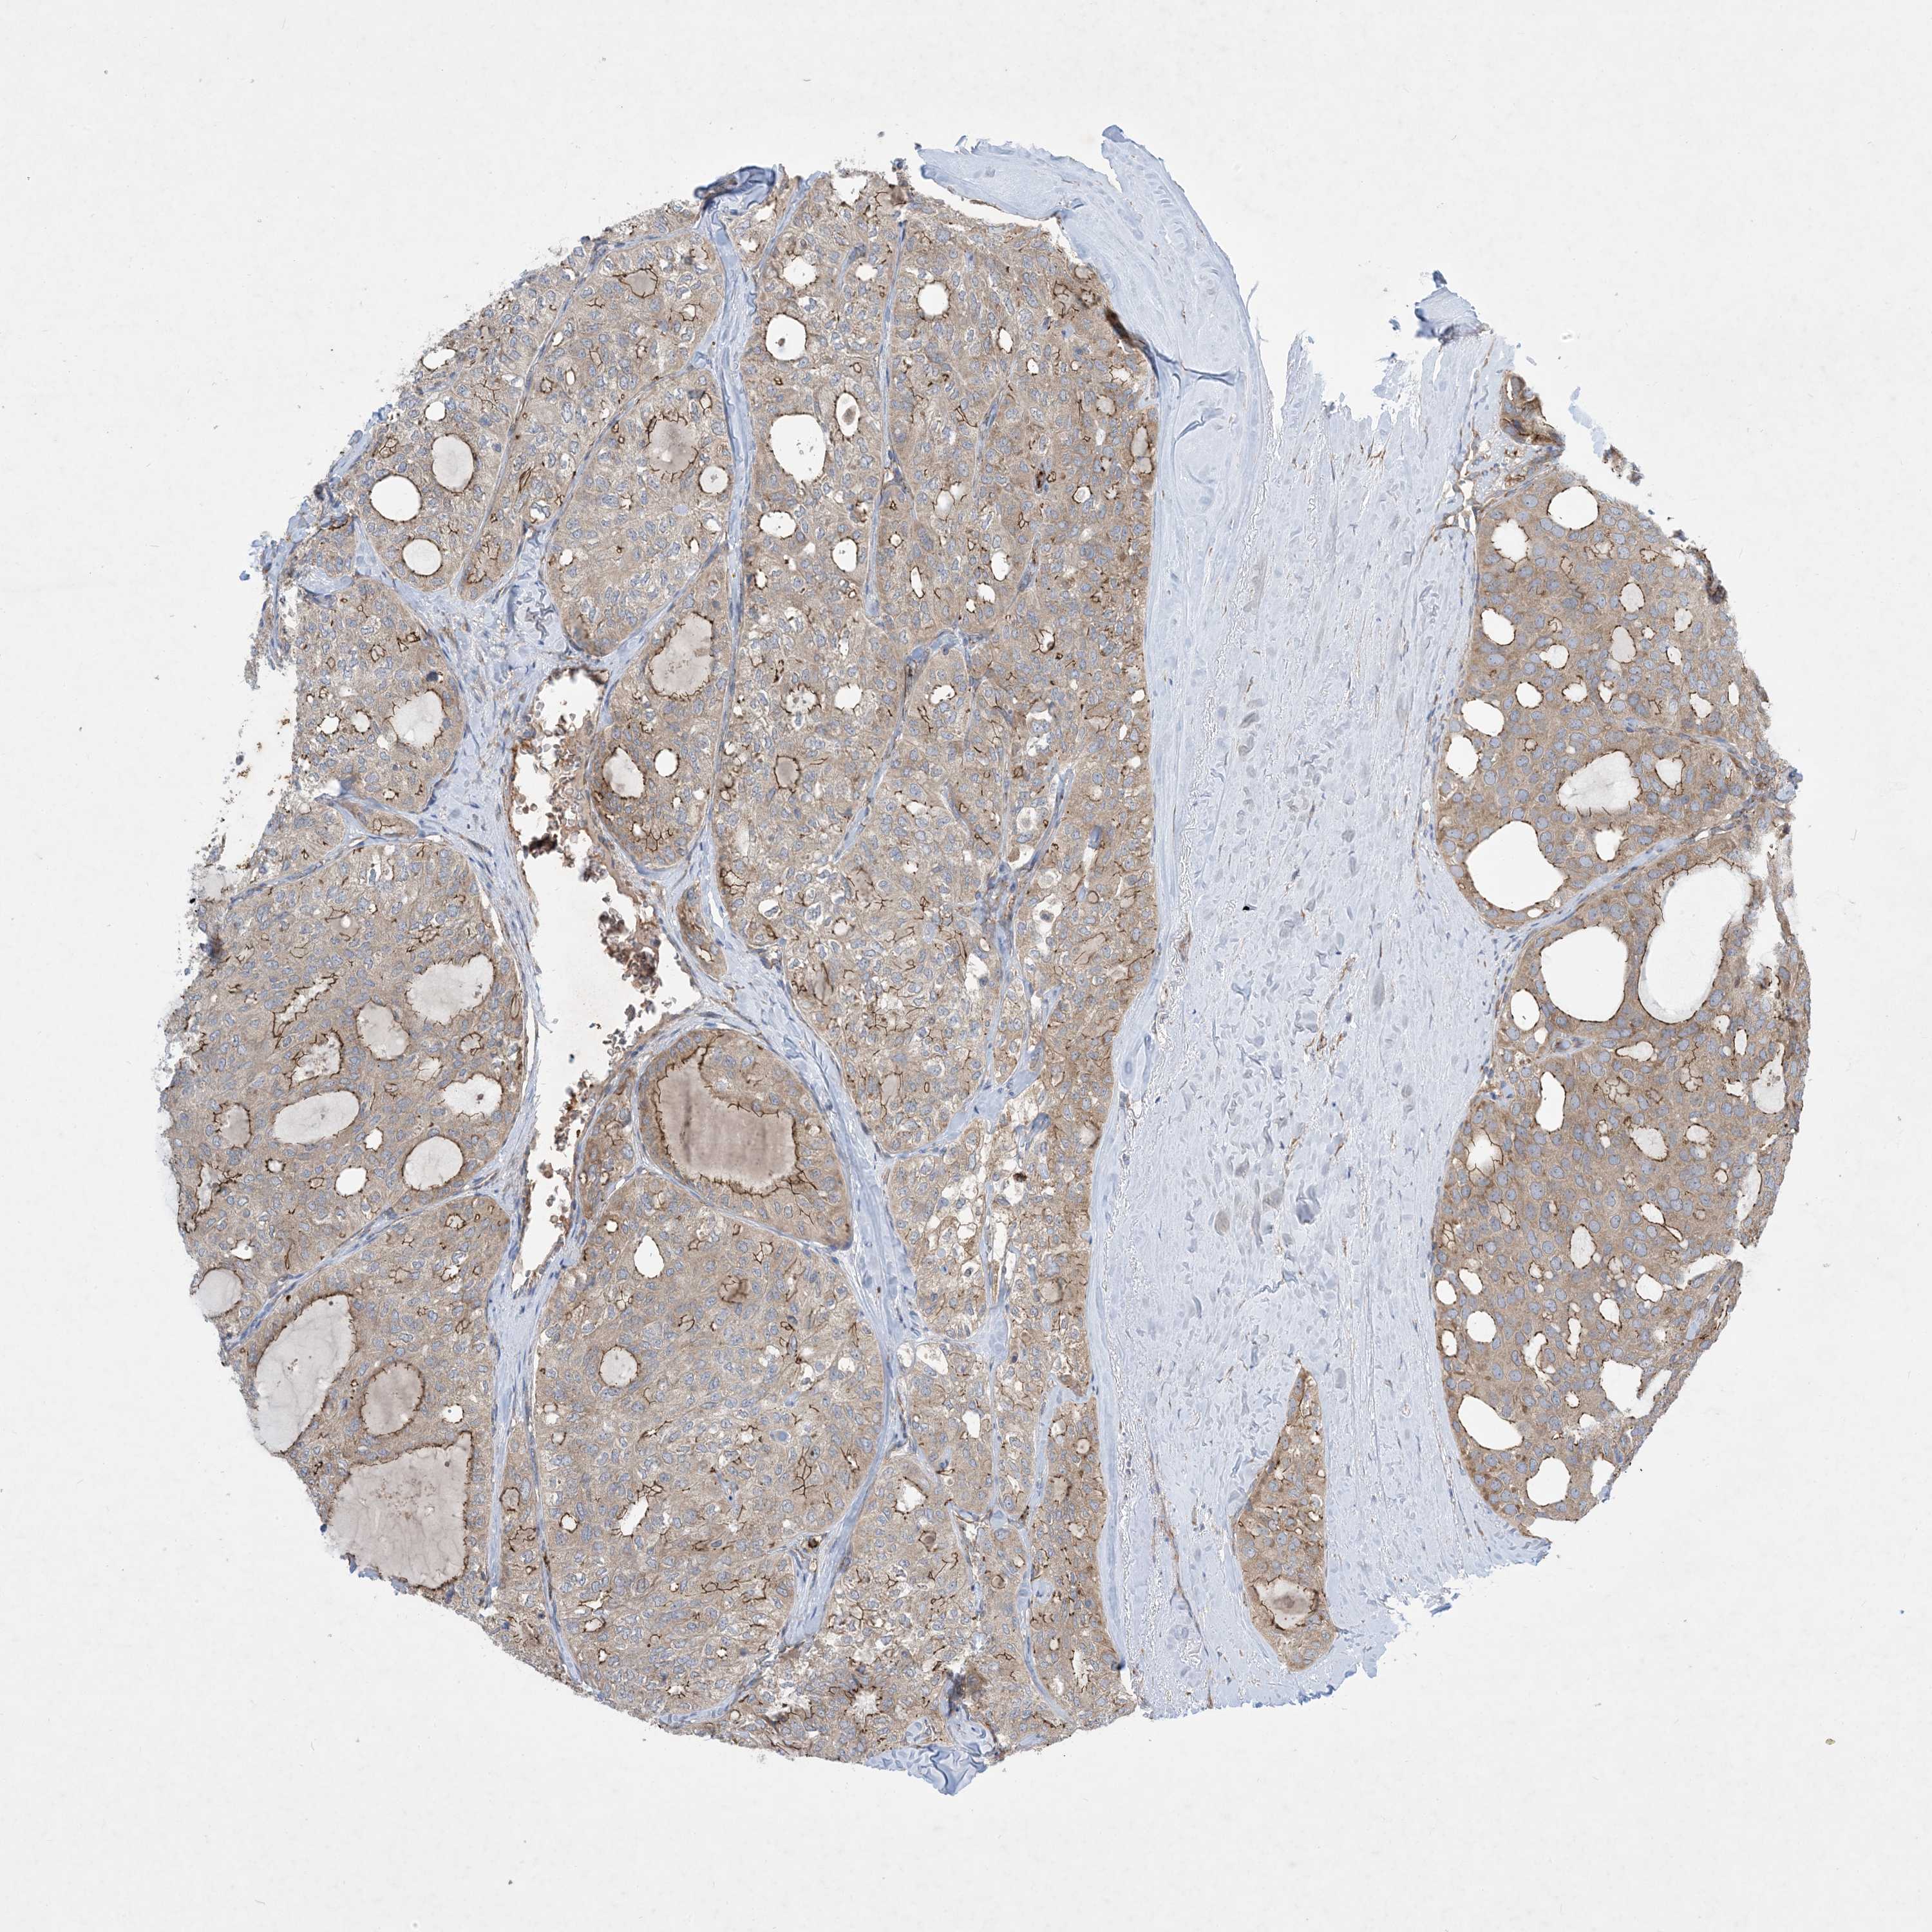

THYROID CANCER - Protein expressioni

A mouse-over function shows sample information and annotation data. Click on an image to view it in a full screen mode. Samples can be filtered based on level of antibody staining by selecting one or several of the following categories: high, medium, low and not detected. The assay and annotation is described here.

Note that samples used for immunohistochemistry by the Human Protein Atlas do not correspond to samples in the TCGA dataset.

Antibody stainingi

Antibody staining in the annotated cell types in the current human tissue is reported as not detected, low, medium, or high, based on conventional immunohistochemistry profiling in selected tissues. This score is based on the combination of the staining intensity and fraction of stained cells.

Each image is clickable and will lead to virtual microscopy that enables deeper exploration of all samples and also displays staining intensity scores, fraction scores and subcellular localization as well as patient and tissue information for each sample.

Antibody HPA035599

Staining

High

Medium

Low

Not detected

Intensity

Strong

Moderate

Weak

Negative

Quantity

>75%

75%-25%

<25%

None

Location

Nuclear

Cytoplasmic/membranous

Cytoplasmic/membranous,nuclear

Papillary adenocarcinoma, NOS

Follicular adenoma carcinoma, NOS